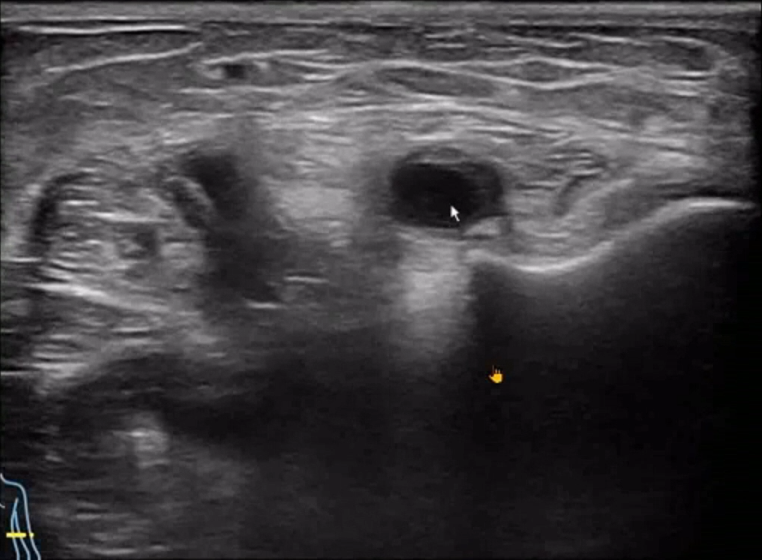

A patient presented with pain and discomfort in the elbow following internal fixation surgery for an olecranon fracture, with a displaced screw.

The ultrasound machine revealed ulnar nerve compression at the cubital tunnel, joint effusion in the left elbow, and synovial proliferation.

In this case, the use of a portable ultrasound machine was crucial for visualizing the precise location of the nerve compression and assessing the synovial changes, enabling targeted treatment planning.